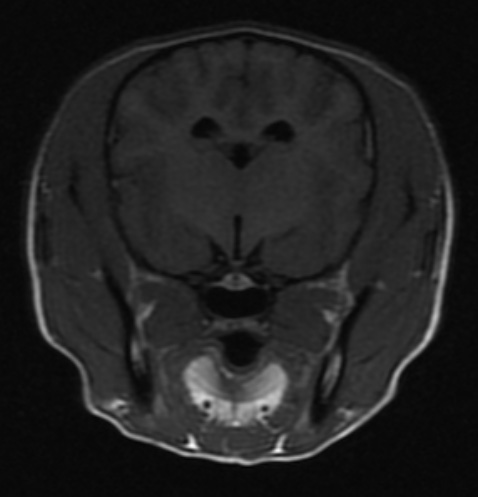

자기공명영상(MRI) 검사

MRI는 자기장 내에서 신체에 고주파를 전사해 반향되는 전자기파를 측정 및 재구성하여 영상을 얻어 질병을 진단하는 검사로, 일반 방사선 검사(x-ray), 전단화 단층 촬영(CT)과 비교하여 방사선 피폭이 없고, 영상 대조도 및 해상도가 연부 조직과 뇌 검사에 뛰어난 장점을 가집니다. MRI는 뇌수두증이나 뇌종양 등 두개내 질환, 디스크탈출, 척수 질환 및 관절염과 인대 파열 등의 관절 질환의 평가에 유용하며 병변의 정확한 진단에 도움을 주고, 이를 통해 이후 빠른 내∙외과적인 치료를 가능하게 합니다.